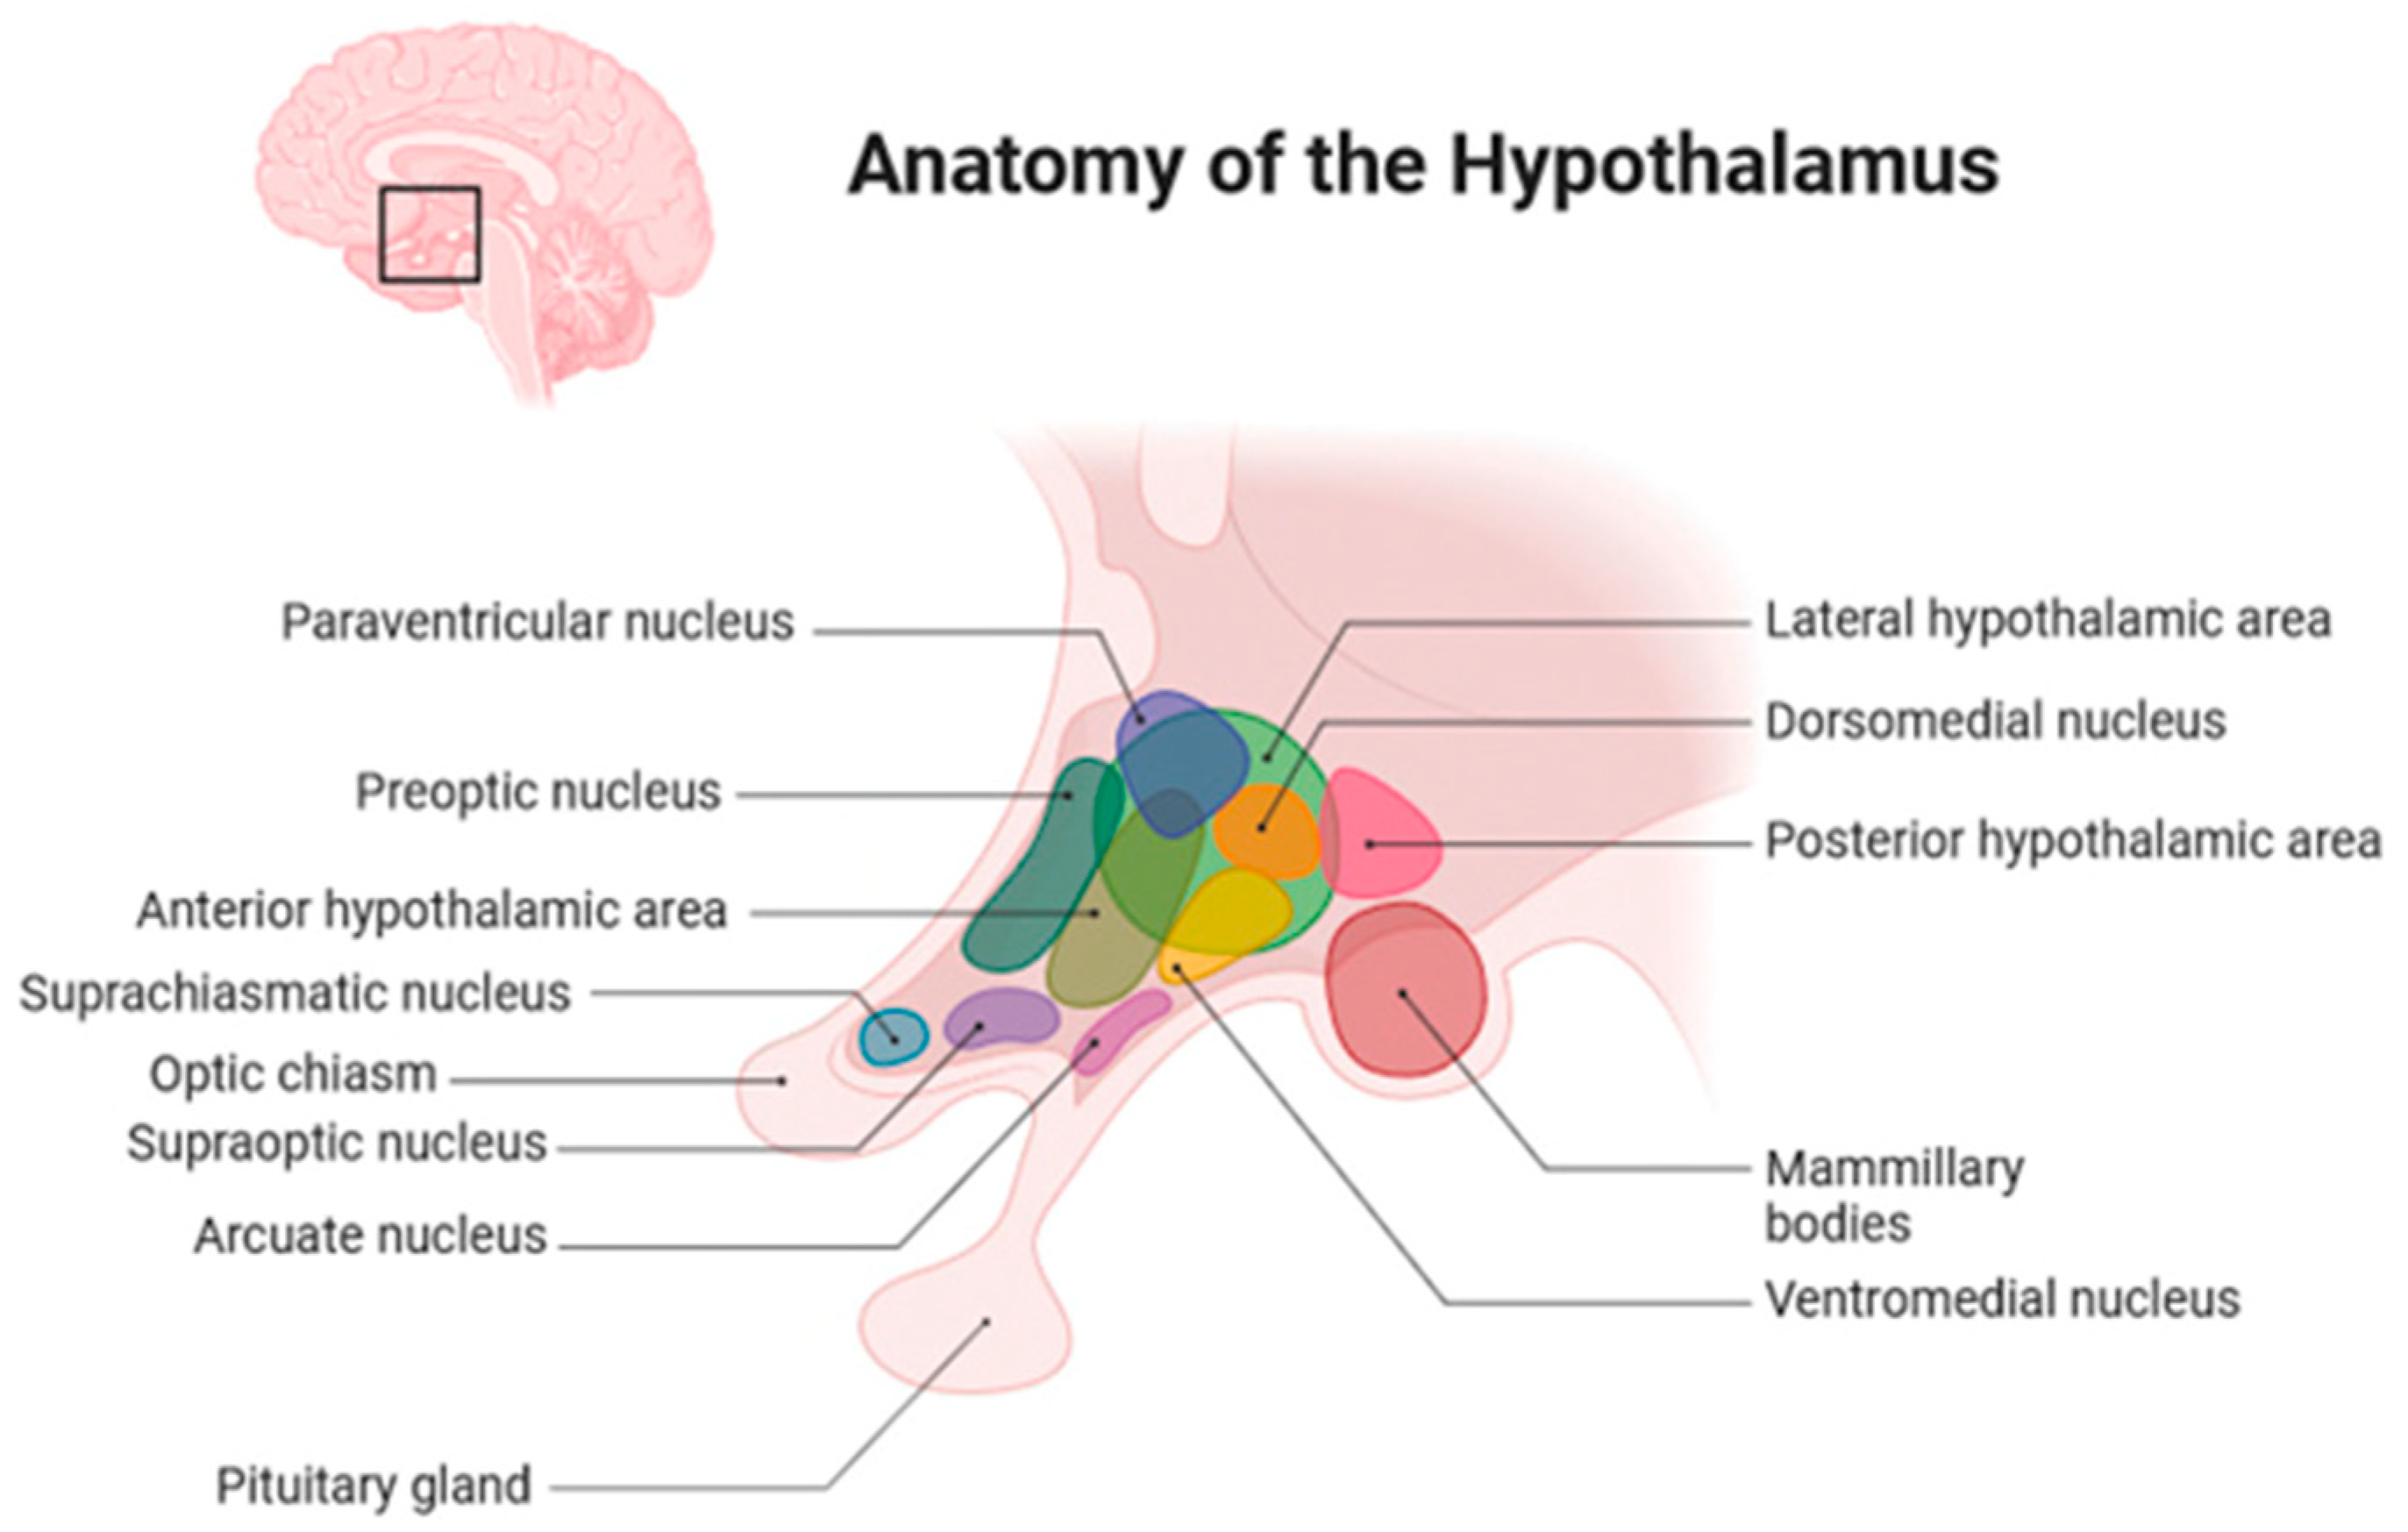

2. Anatomical Location of Childhood-Onset Craniopharyngioma Close to the Hypothalamus